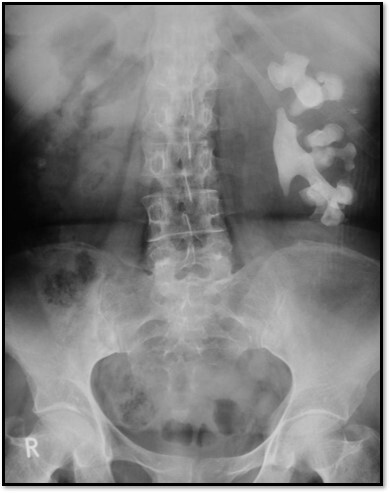

4

Q

What pathology is seen here?

A

Unilateral Renal Agenesis